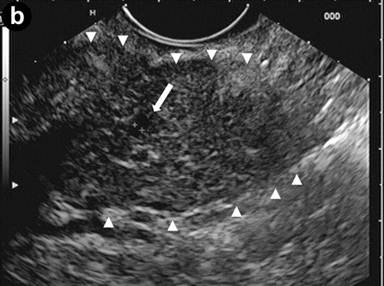

A 24-year-old man presenting with jaundice and elevated levels of IgG4 (366 mg/dL; reference range: 8-140 mg/dL). Magnetic resonance cholangiopancreatography (MRCP) was requested; the T2-weighted coronal scan (Image 1a) showed dilated intra- and extra-hepatic bile ducts with an abrupt stricture (arrow) of the intrapancreatic common bile duct; the pancreatic duct was narrowed throughout its course. Subsequent EUS (Image 1bc) revealed a diffusely and substantially enlarged pancreatic gland (arrowheads) with echopoor echotexture and a normal main pancreatic duct having a diameter of 1.3 mm (Image 1b, arrow), measured with calipers (Image 1c, arrow). Hyperechoic septa were well visible in the enlarged gland. Stenosis of the distal bile duct was due to a diffuse thickening of the wall with an intermediate echopoor layer, and echorich outer and inner layers ("sandwich-pattern") (Image 1d, arrowheads).